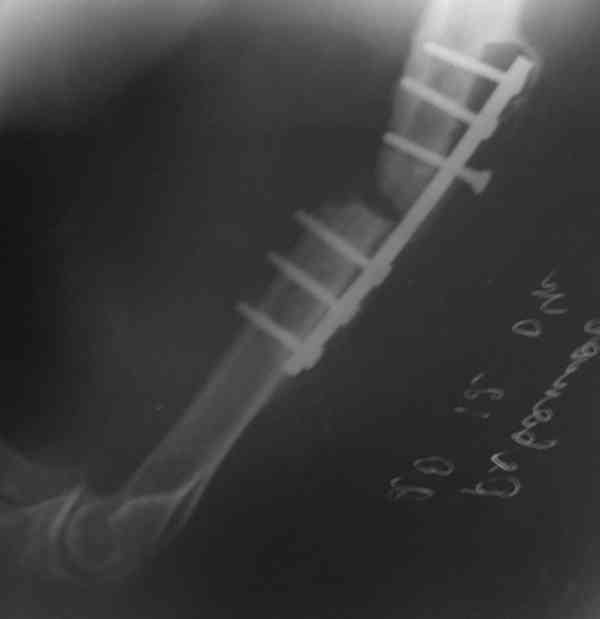

Штифт - отвисание проксимального отдела - накостный остеосинтез, нагноение, АФВ с ревизиями раны, опять пластина и снова нестабильность. Была удалена пластина и выполнен БИОС штифтом ChM (ДЕОСТ). Через 2 нед. пациент сел за руль и вышел на работу. Причем так и работает до сих пор уже 1,5 года, хотя полного сращения мы вроде бы не достигли ( снимки пришлю позже) - пациент не приходил на осмотры, общался только по телефону.